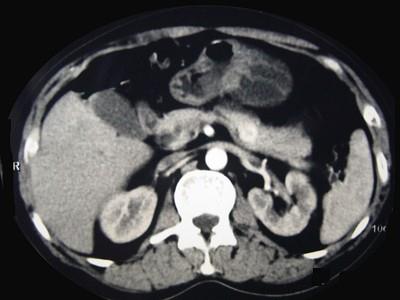

问题 男性,57岁,1年前无明显诱因反复出现嗜睡及发作性神志不清,进食糖水或甜品后症状即缓解,腹部CT检查如下图,最佳的诊断是 ( )

选项 A、胃泌素瘤 B、舒血管活性肽瘤 C、胰岛细胞瘤 D、胰腺转移瘤 E、胰腺癌

答案 C